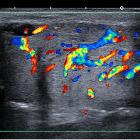

parotid anomalies in infants and children. Acute viral right parotitis. Enlarged, hypervascularized parotid on ultrasonography